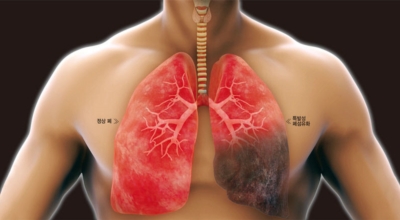

5. 긴 시간의 흡연은 기도의 보호 메커니즘을 훼손시켜 기관, 기관지, 폐 간질 및 폐에 훼손을 주어 폐 기능의 건강에 영향을 미쳐요.

인체가 순조롭게 기능을 발휘하려면 폐 건강이 필수다. 폐는 인체가 효율적으로 움직이는 데 있어 바퀴 안에 있는 톱니 같은 역할을 하기 때문이예요. 산소를 제공하는 폐 기능이 감소하게되면 폐렴이나, 만성 폐쇄성 폐질환(COPD), 천식 등 정도가 심한 호흡기 질환 발생 위험이 증가해요. 이런 질병들은 폐를 공격해 숨쉬기 힘들게 만들어요.

특별히 현대 사회에서 폐는 가장 시달리는 장기 중 한 종류다. 가지가지 공해 성분으로 오염된 공기에 미세 먼지, 황사까지 더하면 폐 안쪽에 있는 허파꽈리(폐포)부터 정도가 심한 훼손을 입습니다. 따라서 폐 건강을 증진시키기 위하여는 폐에 좋은 음식을 섭취할 필요가 있어요.